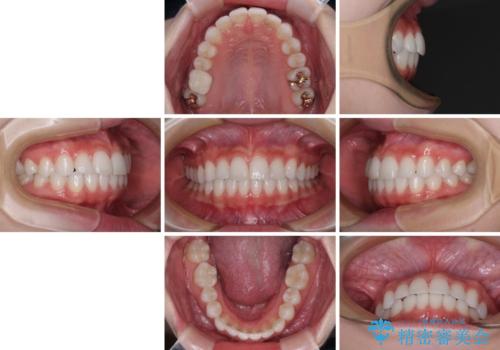

- 歯並びと虫歯をきれいにしたいとのことで来院された患者様です。

楽して短期間で歯列を整えたいとのことで、ワイヤー装置を用いて矯正治療を行い、矯正治療後に下顎の虫歯はセラミックインレー、上顎はPGAインレー(ゴールドインレー)、根管治療を行う歯についてはオールセラミッククラウンにて補綴治療を行うこととしました。

矯正治療は8ヶ月ほどで終了し、速やかに虫歯治療に移行することができました。

保険治療で用いる樹脂(コンポジットレジン)で行った虫歯治療は、周辺が変色して汚くなっていましたが、下顎はセラミックインレーで審美的に、上顎はPGAインレーで歯に負担の少ない治療を行うことができました。